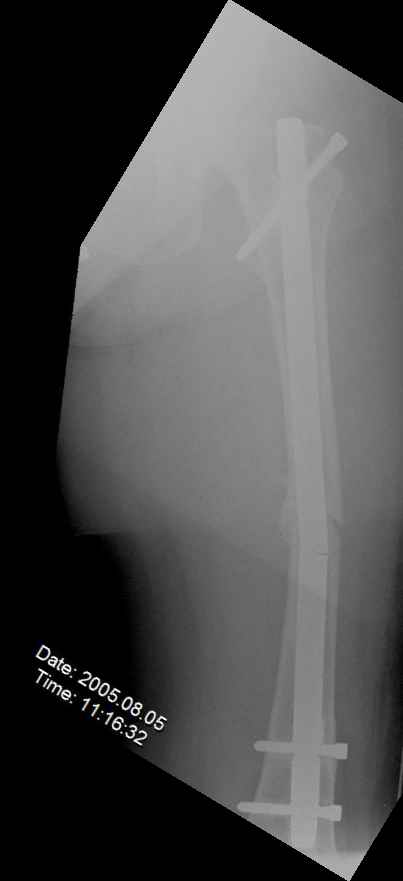

May I have some advice on the following case? Middle aged woman, No chronic medical problems, +tobacco use - but she promises she's going to quit! Original MVC in late 1990's, initial rod failed, and 2 subsequent exchanges failed (most recently shown in attached jpgs.)

Most recent one (6/2002) was apparently an open nailing to remove last broken nail, but no grafting was performed in conjunction. Now sent to me with broken 14mm R/T nail in place.WBC, Hgb, Chemistries normal.ESR 34CRP 4.2No other apparent locus of infection.I was considering a staged approach - removing nail and screws and obtaining cultures.If negative, proceed with exchange nailing with open grafting +/- BMP, But how best to deal with that pedestal distally and avoid anterior breech near patella? If positive cultures, what would be best option?Thanks. Tom Schaller Kalamazoo, MI.

In my opinion, there is no nail strong enough to tolerate a varus deformity of femur after nailing. The AP view of the distal femur shows that the femur has been repeatedly nailed in varus. The tip of the nail is short and lateral in distal lateral metaphysis. It should be central over the intercondylar notch and buried in the distal epiphyseal scar. This has resulted in constant bending forces on the nail (see the "windshield wiper" sign) and its eventual fatigue failure.

I would first determine the degree of varus deformity with a long standing AP x-ray. After nail removal, irrigation, debridement and reaming of the nonunion, specimens would be sent for pathology and culture. If there was any sign of infection, placement of custom made antibiotic nail e.g.

My first definitive treatment choice would be a long lateral tension band plate with insertion of proximal screws directed proximally at an angle of about 25-30 degrees. Correction of the varus would be accomplished by using a tensioning device distally or compressing with two eccentrically placed distal screws simultaneously as shown in Lawrence Webb's OTA BFC lecture